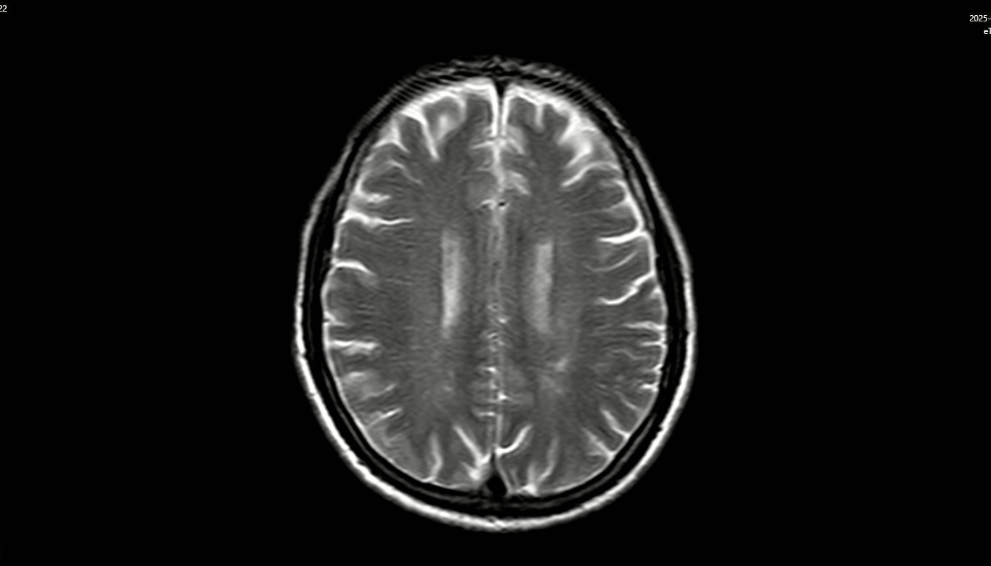

MRI sọ não:

Hình 3: MRI sọ não chưa phát hiện tổn thương thứ phát